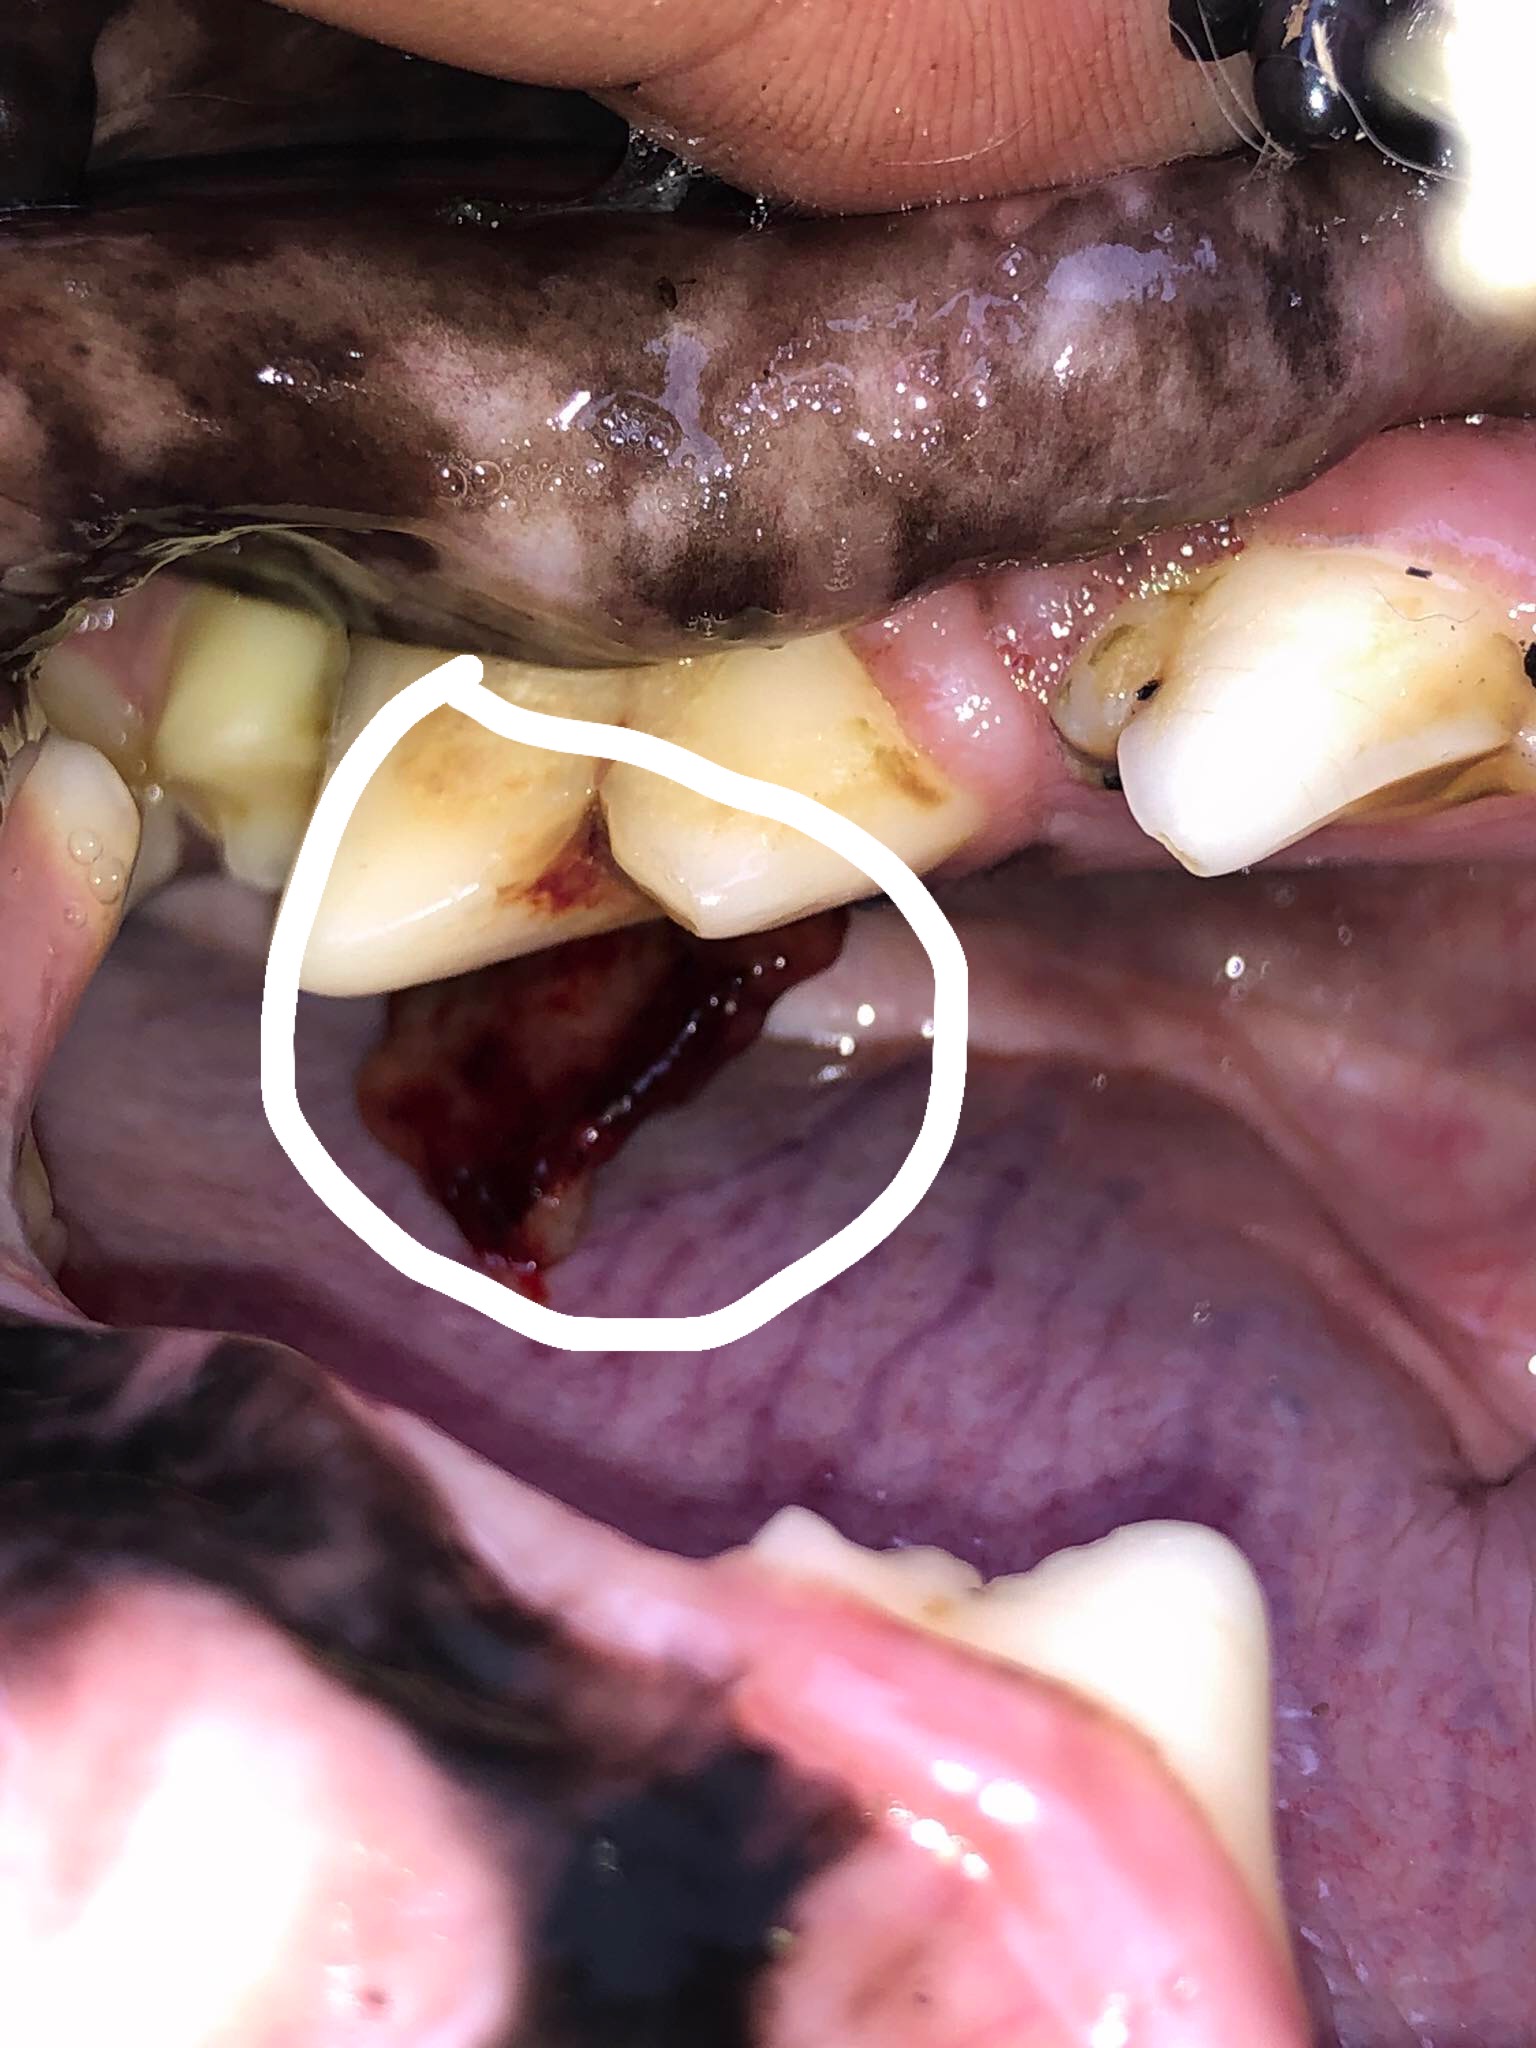

Dobrý den, prosím o radu než se dostaneme k našemu veterináři. Našemu 10 let zlatému retrieverovi začalo při kousani klacku krvacet z tlamy. Při prohlídce tlamy jsem objevila asi nárůstek na spodní čelisti na vnitřní straně zubů. Posílám fotku a prosím o radu co by to mohlo být. Moc dekuji.

Dobry den, z fotky tezko rict. Muze to byt cizi teleso, muze to byt odemrela cast dasne, ktera byla poskozena. Jako nador to moc nevypada. Ale musite to nechat posoudit naživo :)